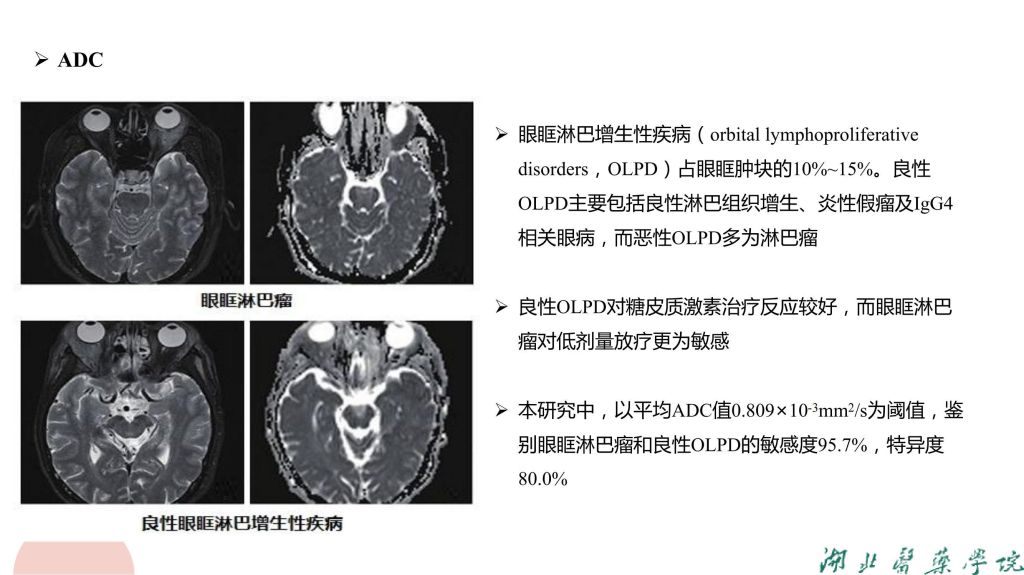

病例分析-眼眶淋巴瘤